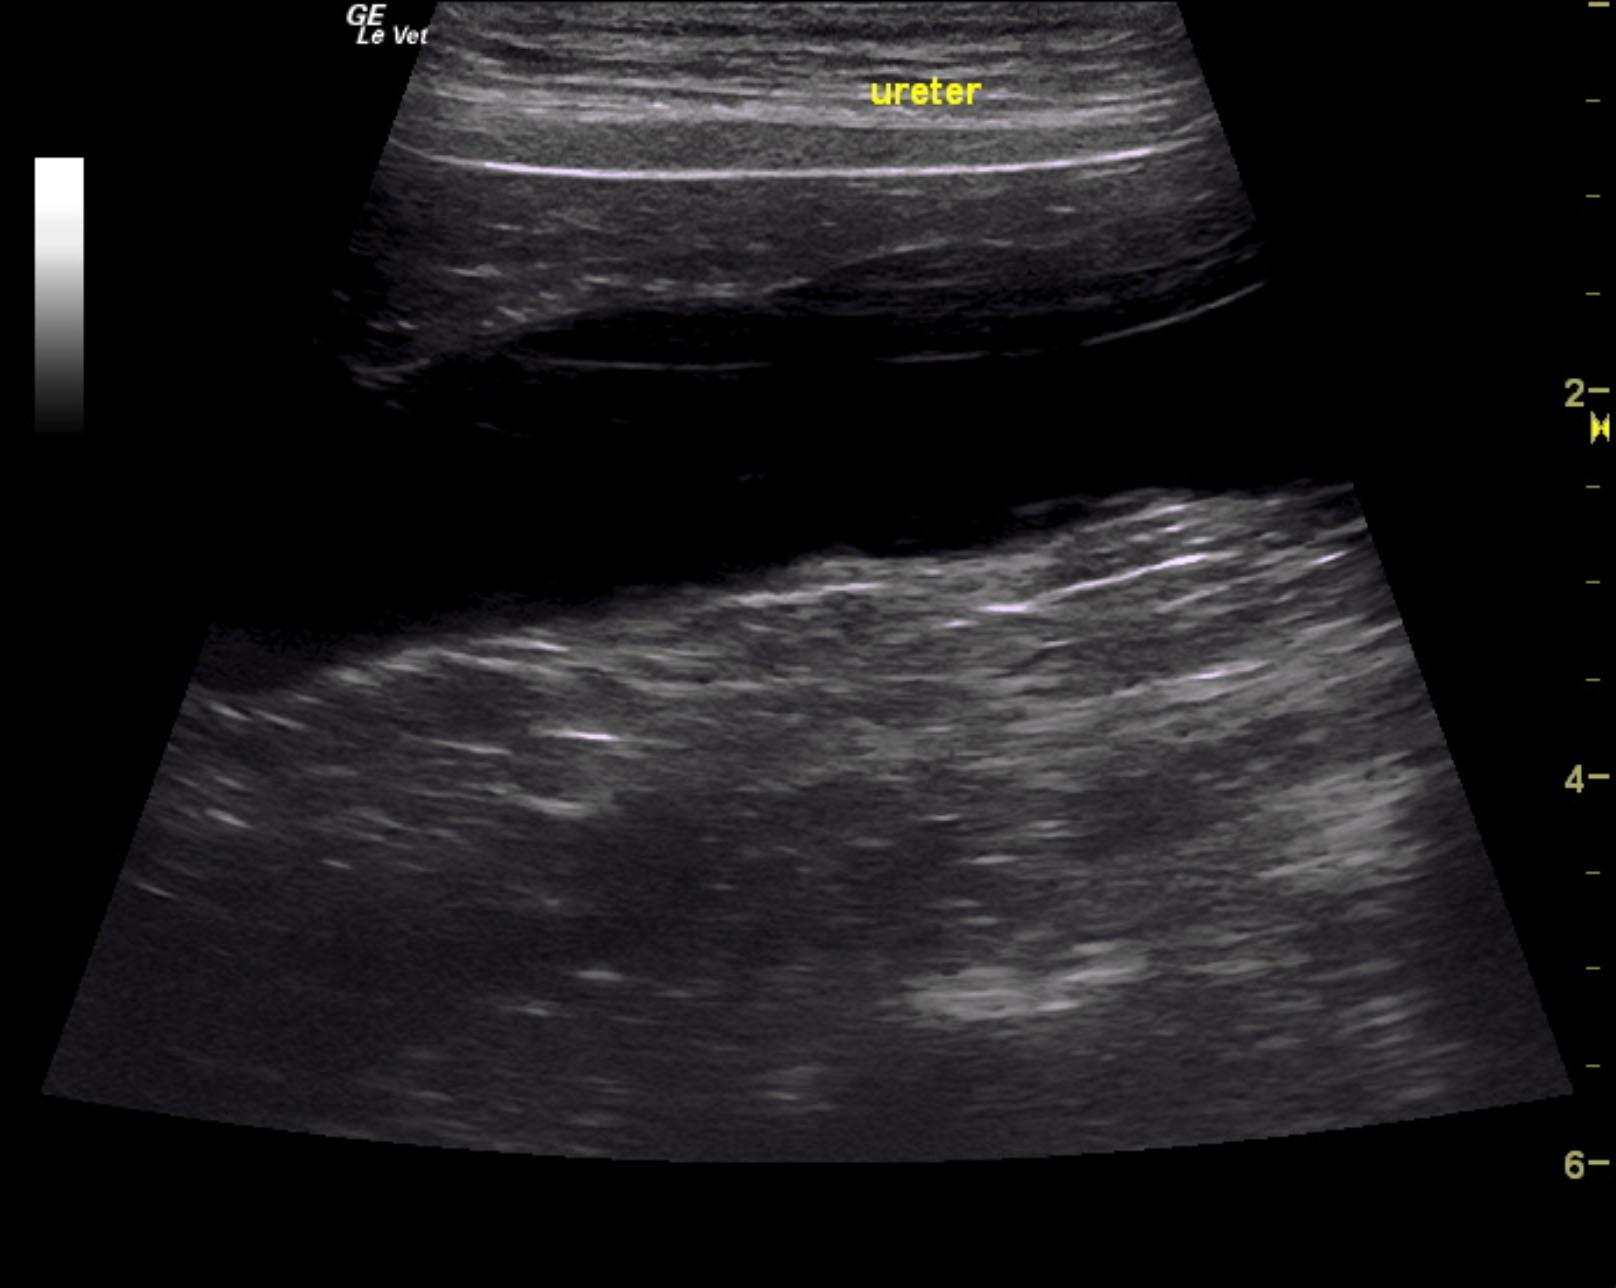

A 1-year-old neutered male Labrador retriever dog was presented for evaluation of urinary incontinence. Urine specific gravity was 1.039, and bloodwork was within reference range.